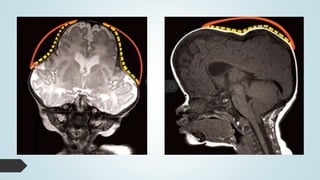

RNM

 Anomalidades

 Chiari

 Hidrocefalia

• #14 A) asimetría de los ventrículos (flecha) y B) disminución de la densidad del parénquima cere- bral e hipoplasia cerebelar (flechas). TAC de cráneo con reconstrucción tridimensional: